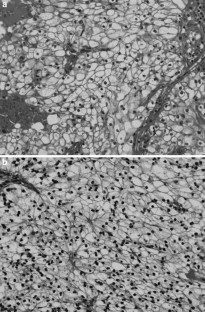

Fig. 3